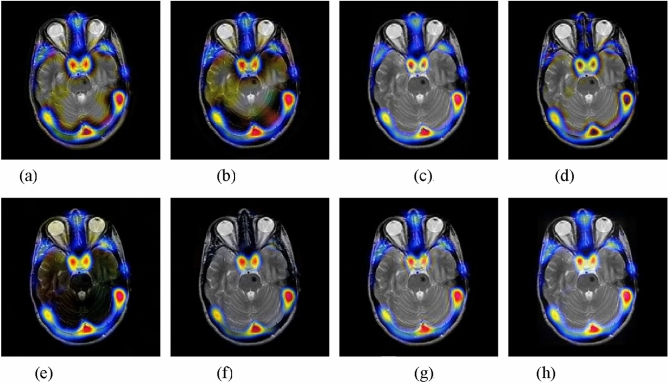

MR-T1 and MR-T2 image fusion

The fourth experiment is conducted on MR-T1 and MR-T2 images. The fused results of different fusion approaches are presented in Fig. 6. The NSST-PCNN, SR, and MST-SR methods suffer from detail loss in the fused results. The NSST and DSWT-RBFN methods fail to well inject the MR-T2 image into the fused images. The GFF method cannot well integrate the details from MR-T1 image. By contrast, the proposed method can effectively merge the MR-T1 and MR-T2. Furthermore, Table 4 lists the objective metrics of all approaches on 11 pairs of MR-T1 and MR-T2 images. It is obvious that the proposed method still obtains the highest fusion results in terms of four indexes, which further illustrate the effectiveness of the proposed method.

Figure 6.

Fusion results of different methods for MR-T1 and MR-T2 images. (a) CNN-NSCT. (b) NSST. (c) NSST-ST. (d) SR. (e) MST-SR. (f) GFF. (g) DSWT-RBFN. (h) Our method.